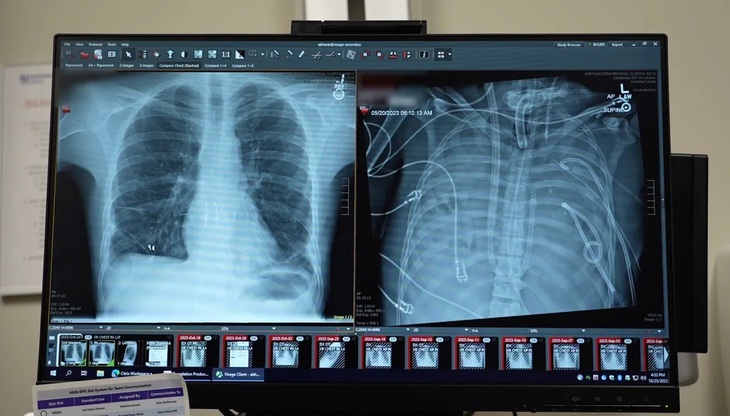

Các bác sĩ Đại học Northwestern tiến hành cắt bỏ phổi hoại tử và gắn phổi nhân tạo, trước khi ghép phổi hiến tặng vào hai ngày sau đó - Ảnh: NORTHWESTERN UNIVERSITY

Bệnh nhân khỏe mạnh bên lá phổi mới được ghép (trái) và lúc đã cắt bỏ phổi hoại tử - Ảnh: NORTHWESTERN UNIVERSITY

Kết quả cho thấy ngay sau khi phổi được cắt bỏ và máu được oxy hóa nhân tạo, chức năng của các cơ quan khác bắt đầu cải thiện. Hai ngày sau, khi có phổi hiến phù hợp, bệnh nhân đủ điều kiện để ghép phổi thành công.